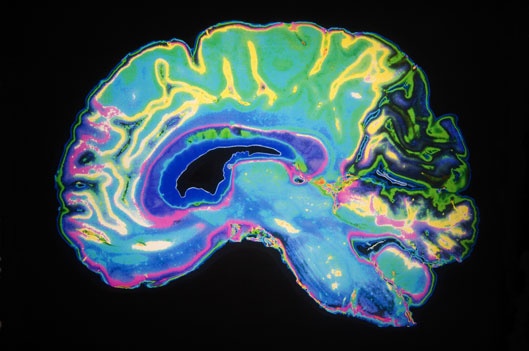

Gene Wilder’s death on Aug. 29 at age 83 from complications of Alzheimer’s disease prompted tributes across generations of fans of the beloved comic actor. It also focused additional public attention on Alzheimer’s, a progressive neurological disease that is the leading cause of dementia.

The doctors say that people usually begin showing signs — such as misplacing items, having difficulty keeping track of events, or repeating questions — five to 10 years before they’re diagnosed. The changes in the brain caused by the disease may begin occurring decades before symptoms even appear.

“Those changes start happening for most of us in the midlife period,” Shah says, “Our brains are so resilient that it protects itself, and it takes a long time before Alzheimer’s becomes symptomatic.”